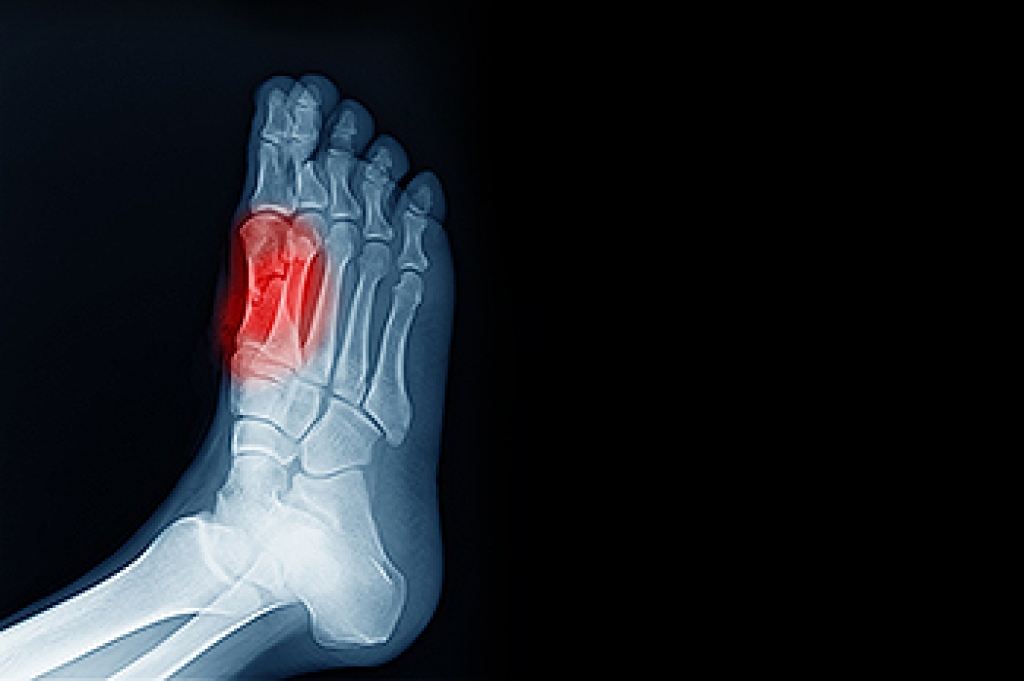

Leading the way in diabetic limb salvage, surgical treatments by using state of the art research and technology.

The Institute of Foot & Ankle Reconstructive Surgery, with offices in Merrillville and Munster, IN , is dedicated to getting to the root of your foot or ankle problem.

Our podiatrists, Dr. Ahmad Elsamad, MS, DPM, FACAS, and Dr. Rani Dabal, DPM specializes in ingrown toenails, diabetic foot care, and rearfoot and forefoot surgery. Having chronic foot and ankle pain can greatly affect the quality of your life, and we understand that. We also know how hectic life can be, and we’re committed to making our practice and care convenient and accessible.